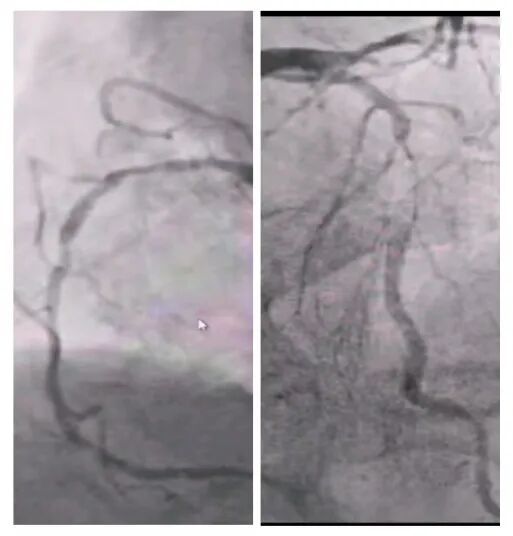

術(shù)前冠脈造影

2025年深秋的一個(gè)清晨,82歲的馬奶奶(化名)因持續(xù)胸悶氣短被家人送至醫(yī)院心內(nèi)科。心臟超聲檢查顯示,她的左心房內(nèi)有一個(gè)直徑近5厘米的腫瘤,隨心跳規(guī)律擺動,如同一個(gè)隨時(shí)可能破裂的“不定時(shí)炸彈”。更危急的是,冠脈造影進(jìn)一步揭示其冠狀動脈多支血管嚴(yán)重狹窄,左前降支狹窄達(dá)95%,回旋支中段完全閉塞,右冠狀動脈彌漫性病變—兩種致命性心臟疾病的疊加,讓這位高齡患者的生命岌岌可危。